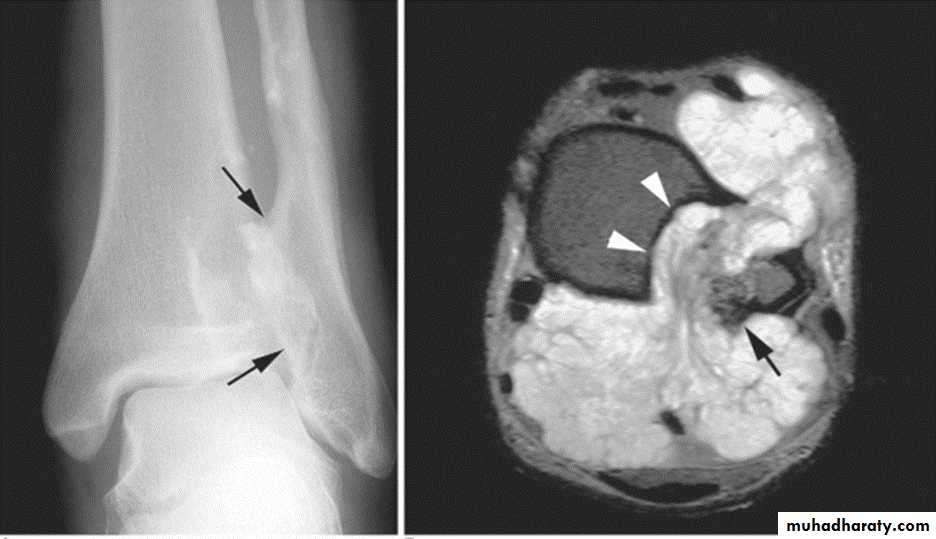

Giant cell tumor:Slowly growing , locally invasive, rarely metastasize.

Age: after closure of epiphysis (20-40 years).

Site: around knee & wrist joints.

Findings:

lytic, expansile lesion,

Sub articular in location,

Not clearly defined margin,

thinning of the cortex (sometimes with destruction of cortex)